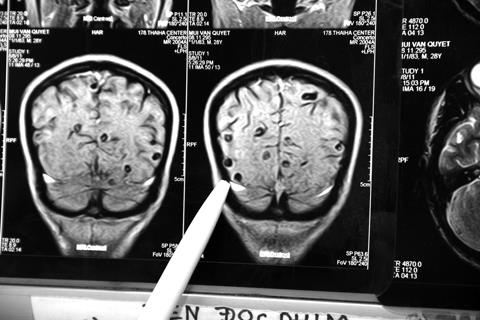

BS Nguyễn Trung Cấp, khoa Cấp cứu, Bệnh viện Bệnh nhiệt đới Trung ương, cho biết bệnh liên cầu lợn gồm 3 thể là nhiễm trùng huyết, viêm màng não mủ hoặc kết hợp cả hai.

Bệnh diễn tiến rất nhanh, tỷ lệ tử vong có thể lên tới 20%. Nếu chữa khỏi, 40% vẫn để lại di chứng nặng nề, phổ biến nhất là điếc và các di chứng thần kinh, nhiều trường hợp phải cắt cụt tay, chân.

Theo BS Cấp, khi nhiễm liên cầu lợn, người bệnh có biểu hiện sốt nóng, sốt lạnh, đi ngoài (nhưng không nhiều lần) khiến nhiều người lầm tưởng với các rối loạn tiêu hóa. Người bệnh cũng có biểu hiện tri giác lơ mơ, li bì hôn mê, bệnh nhân sốc tụt huyết áp, xuất hiện các ban hoại tử trên da do nhiễm trùng huyết khiến tay chân hoặc toàn thân tím, đen.

Một số trường hợp nguy kịch có diễn biến nhanh và nặng với biểu hiện sốc nhiễm khuẩn, suy đa tạng, rối loạn đông máu…